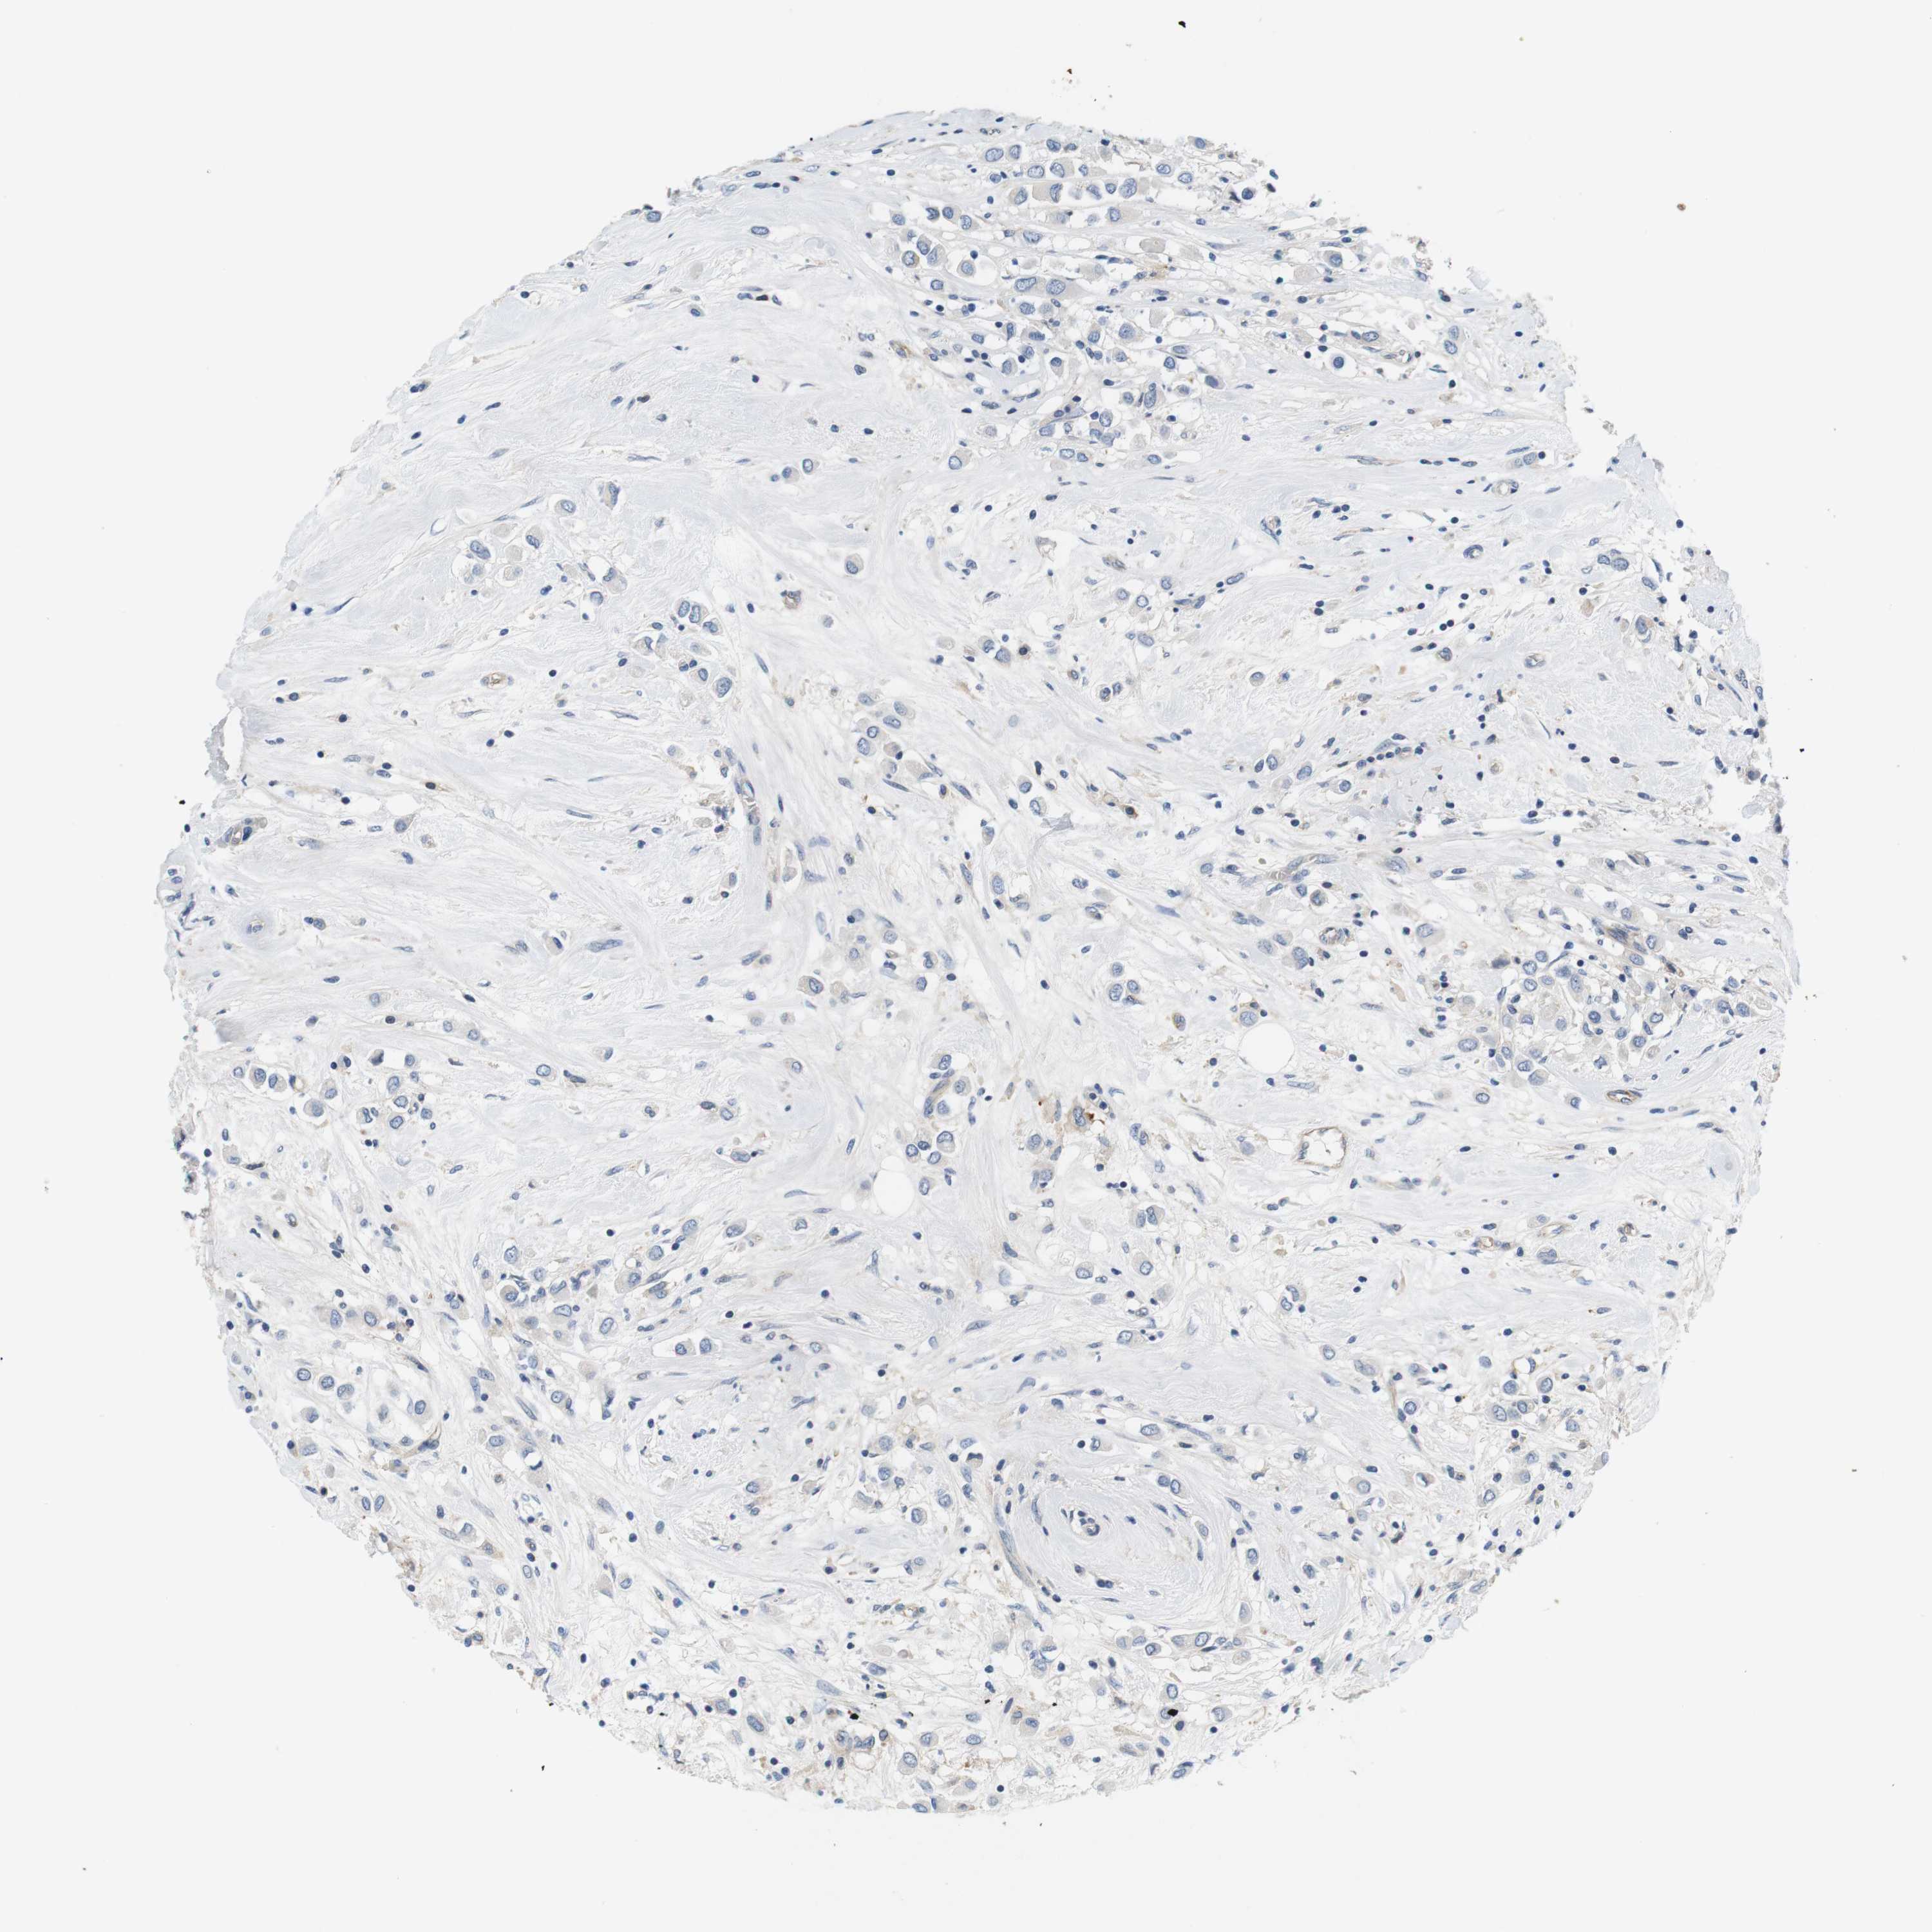

CANCER BREAST CANCER Show tissue menu

BRCA TCGA BRCA VALIDATION PROTEIN EXPRESSION

Breast cancer

Human cancer